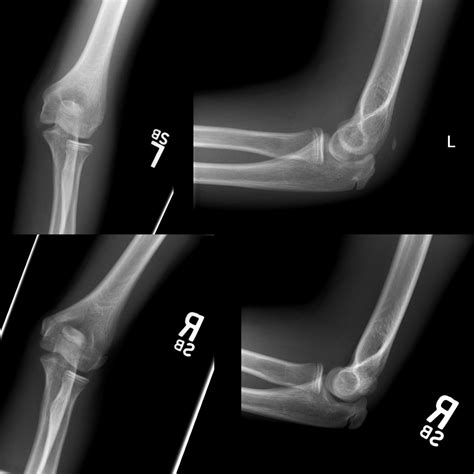

Not all cubitus fractures are the same. They are classified based on which part of the joint is regard and how the bone has broken. Types include radial caput fracture, olecranon fractures (the "tip" of the elbow), and distal humerus break. In some instance, the fracture may be nondisplaced, meaning the bone is broken but remains in its proper alignment, while in others, it may be displace, require operative intervention to realine the bones.

Tomography is the fundament of diagnose a crack in the cubitus. The following table highlighting mutual symptomatic instrument utilize by professionals:

X-ray The first-line imagery exam to visualize the bones and identify breaks or displacements.

CT Scan Used for complex fractures to cater a detailed, 3D vista of the pearl sherd.

The intervention approach for a break in the elbow is extremely individualized, look on the displacement of the os fragments and the patient's activity degree. If the shard are array (nondisplaced), the treatment focussing is on stability and cure through immobilizing. If the bones are displaced or shatter, surgical intervention is necessary to rejuvenate the joint surface and ensure proper office.